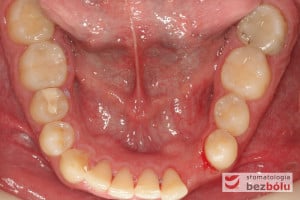

Młody pacjent w wieku lat 28 po wstępnym rozpoznaniu, ze zdiagnozowanym złamaniem kła zarówno górnego jak i dolnego, został skierowany na terapię implantoprotetyczną, prowadzoną przez lekarza dentystę Marcina. W świetle braku możliwości wykonania ekstruzji ortodontycznej i zachowawczego podejścia do leczenia, podjęto decyzję o usunięciu obu zębów, zastosowaniu ułatwiającej gojenie procedury A-PRF i przygotowaniu pacjenta do zabiegu implantologicznego, dodatkowo uzupełnionego o wprowadzenia implantu w miejscu braku zębowego w pEdytujozycji pierwszego przedtrzonowca w szczęce po stronie prawej.

Po zakończeniu procesu gojenia wyrostka zębodołowego, wykonano diagnostykę radiologiczną z zastosowaniem tomografii wiązki stożkowej (CBCT) w celu oceny ilości oraz jakości tkanki kostnej, zarówno w miejscach poekstrakcyjnych, jaki i w pozycji górnego prawego przedtrzonowca. Ponadto pobrano wyciski, oddające sytuację kliniczną w jamie ustnej pacjenta, który zdecydował się na metodę implantacyjną, wykorzystującą nawigację komputerową, z zastosowaniem protokołu MGuide firmy MIS. Procedura ta polega na cyfrowym zaplanowaniu pozycji implantów, a następnie wykonaniu w technice druku 3D szablonu chirurgicznego.Taka metoda pozwala wyeliminować konieczność odwarstwiania płatów, zmniejszając przy tym pozabiegowe dolegliwości. Usprawnia jednocześnie pracę operatora, dokładnie pozycjonując wszczep w pożądanej pozycji. Kolejnym krokiem było przesłanie skanów modeli gipsowych oraz tomografii do siedziby MCenter w Berlinie, gdzie wysoko wyspecjalizowani technicy, dysponujący najnowszą technologią cyfrową, precyzyjnie wykonali szablony nawigacyjne, stosowane podczas zabiegu implantologicznego.